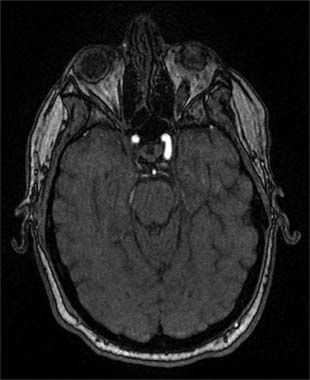

He had no light perception in the right eye and 20/25 vision in the left eye. The right pupil was unreactive to light, with a positive afferent defect; the left pupil was reactive. Visual field was completely obscured on the right; there was a minimal superior altitudinal defect on the left. Dilated funduscopic examination of the right eye showed a pale, resolving, edematous disc without hemorrhages or macular disturbance, such as a star formation. The left optic nerve head had mild edema superiorly and minimal atrophy inferiorly. Ocular motility was normal. MRI findings (shown) were normal, ruling out other causes, such as tumor, infarct, and bleeding. Nonarteritic anterior ischemic optic neuropathy (NAION) secondary to severe hypotension in the setting of sepsis and multiple organ failure was diagnosed.